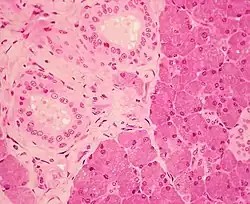

Stratified cuboidal epithelium in the ducts of the parotid gland, visible as the borders of the two circular structures in the upper left. | |

Stratified cuboidal epithelium, highlighting the nucleuses, the rest of the epithelial cells, and underlying connective tissue.

Stratified cuboidal epithelium is a type of epithelial tissue composed of multiple layers of cube-shaped cells. Only the most superficial layer is made up of cuboidal cells, and the other layers can be cells of other types. Topmost layer of skin epidermis in frogs, fish is made up of living cuboidal cells.

This type of tissue can be observed in sweat glands, mammary glands, circumanal glands, and salivary glands.[1][2] They protect areas such as the ducts of sweat glands,[3] mammary glands, and salivary glands. They are also observed in the linings of urethra.